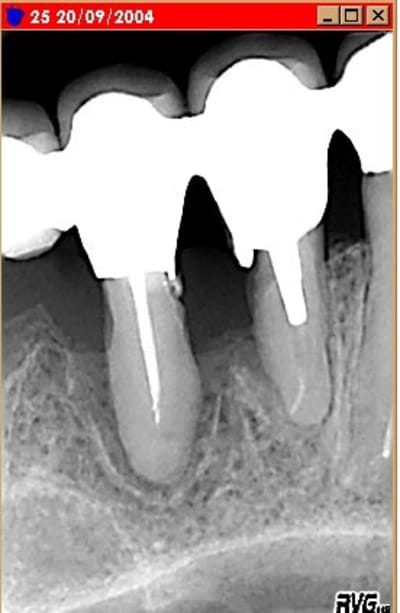

Toutes les questions que vous posez sont très pertinantes et me serviront pour l'avenir. Il y à 2 ans, je n'ai pas regardé l'occlusion, pas trans-iluminé, il y avait aussi un abcès paro au niveau de la 11.

et bien moi je dis bravo ...comme toujours souvent il reste du parodonte . c'est pas gagné car je crains que tes racines aient souffert ( rhyzalyses possibles ..Il y a de tels phénomènes infectieux. ) mais à moins que je sois bigleux je trouve que c'est mieux non et peu importe le système d'attache.c'est ce qu'il fallait tenter de toute façon ........

Alors pourquoi ces lésions la et pas ailleurs ? dans une bouche ou tout semble avoir été réalisé avec les plus grands soins . Je suis pas d'accord avec diplodomaxi....... je suis pas un fou d'endo mais les images sont celles de vieilles endo réalisées par un clinicien consciencieux vu l'ajustage des prothèses qui moi me parait top ....et là manifestement c'est pas un problème endo ...... par contre les effets de l'inflammation sur l'endo......

j'ai regardé à nouveau tes clichés. sur le long terme il faudra surveiller tes dents car l'état de surface vers le collet semble très irrégulier......Il faut que la flore soit surveillée de près.....

bien vu phil. Effectivement, il y a eu une carie en palatin sur la racine de 25. Traitée il y a 6 mois au verre ionomère.

ce qui m'inquiete c'est plus l'état de surface et la souffrance cemento dentinaire liée à l'infection et à l'inflammation . IL faudra que je retrouve ( et scanne )toute les radios d'un cas avec alveolyse + que terminale récupérée et qui 10 ans environ après a à nouveau montré un gros pb car il y avait une rhyzalyse à l'apex .J'ai prolongé la dent 10 ans c'est toujours ca. Mais tu as raison on ne parie pas, jamais sur ces cas .